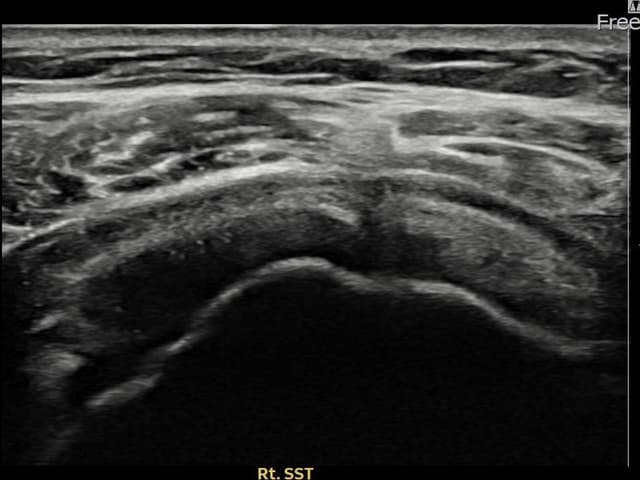

[촬영시기:23.07.31~23.09.27]

[어깨인대 축소봉합술] 좌측 어깨 극상근건 광범위 파열로 수개월간 일상생활이 어렵던 중 내원하셨습니다.